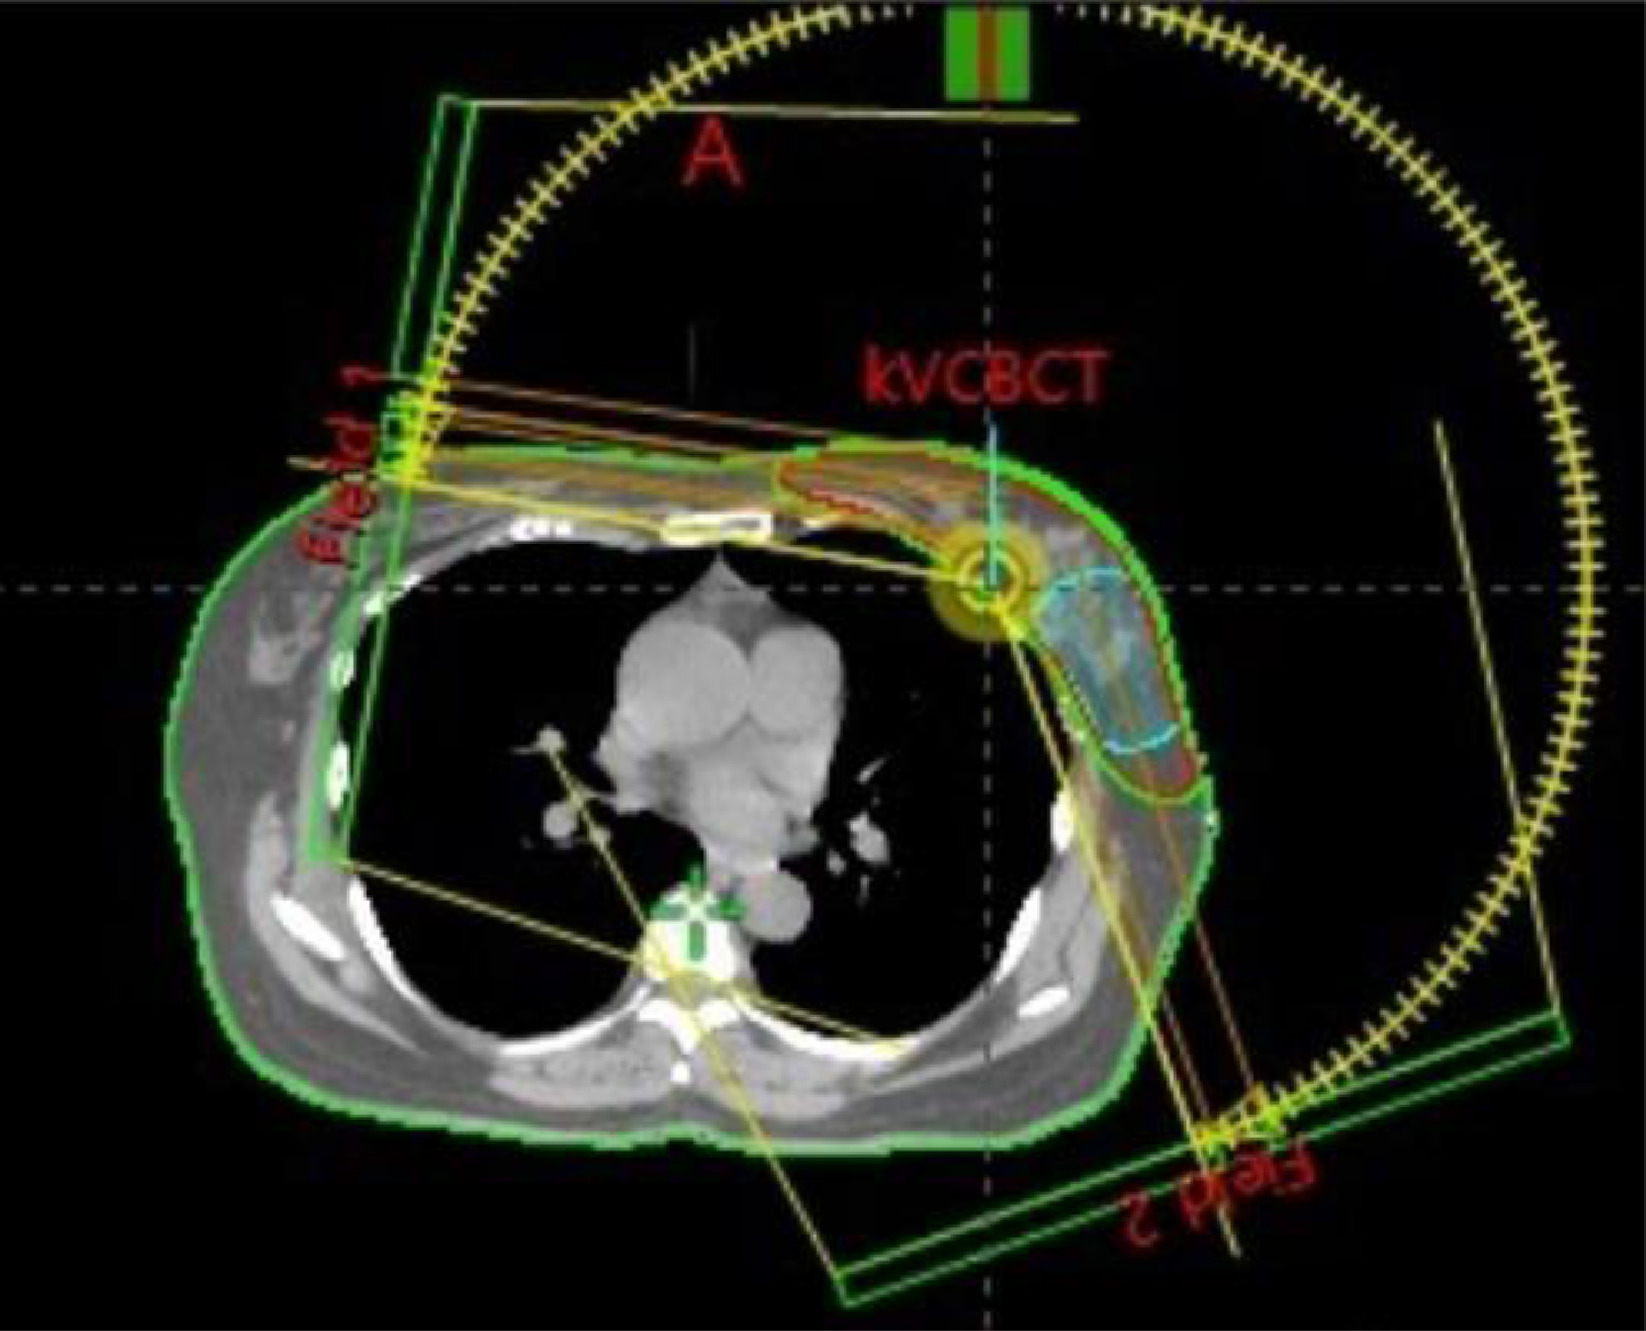

VMAT is a type of radiation therapy that uses advanced technology to treat cancer. Unlike traditional radiation therapy, which delivers radiation from a single angle, VMAT rotates around the patient in a 360-degree arc. This approach allows for precise targeting of the tumor, adjusting the intensity of the radiation beam as it moves, and delivering the optimal dose directly to the cancer cells.

• During a VMAT session, the patient lies still on a treatment table. The machine, known as a linear accelerator, rotates around the patient, delivering radiation in a continuous arc. The intensity and shape of the radiation beam are constantly adjusted to focus on the tumor from multiple angles.